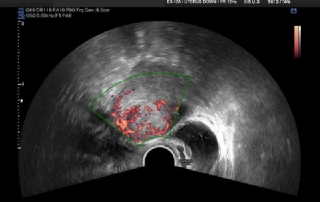

Ellis Downes about hysteroscopic ablation techniques

Video / podcast by Guenter K. Noé MD Phd